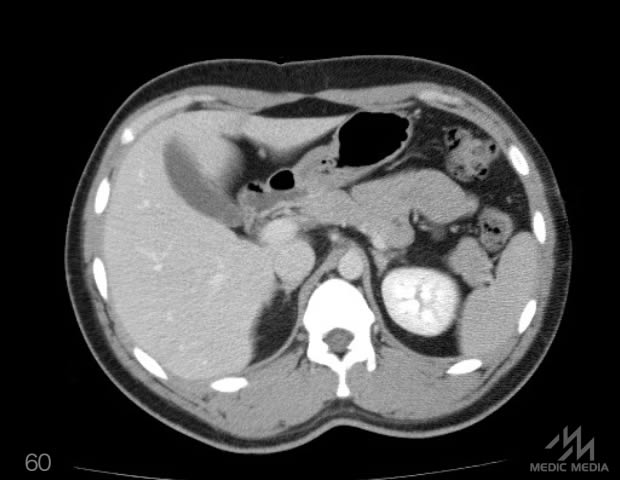

造影CT

消化器

肝区域